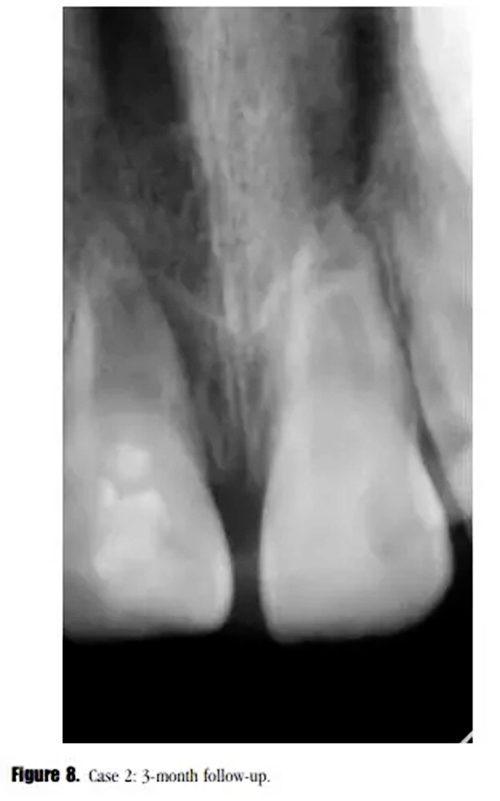

盡管在3個(gè)月的隨訪中,瘺管沒有消失,但是牙齒的癥狀已經(jīng)消失了。X線顯示根尖區(qū)的進(jìn)一步發(fā)育,牙根近中方向有透射性影響。與患者家長(zhǎng)溝通后,1個(gè)月后實(shí)行常規(guī)根管治療。根尖區(qū)放置5mm后的MTA栓,復(fù)合樹脂以及纖維加強(qiáng)樁修復(fù)。少量的MTA從根尖近中方向被壓出。此外,根管系統(tǒng)以及繼發(fā)生成的根尖組織之間可見一明顯的透射影像。(圖8)

在3個(gè)月的隨訪中,患者癥狀消失,X線顯示透射區(qū)愈合(圖9)